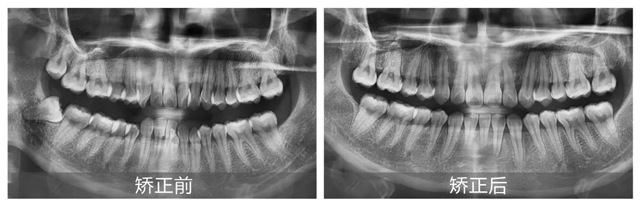

經過詳細面診,并根據口掃、CBCT檢查結果顯示,鄧女士主要面臨的問題有上頜牙列中度擁擠、下頜牙列重度擁擠,并且有一顆下切牙由于長期的擁擠已經出現牙周炎癥狀。

郝璐醫生指出,因為牙齒過于緊密,鄧女士的下前牙排列錯位,形成了咬合創傷,同時伴有牙槽骨吸收和牙齦萎縮的情況。此外,上頜左側切牙和右側尖牙反頜,造成了上下頜牙弓不對稱,上下頜中線不一致,前牙深覆合。這些情況在鄧女士張口說話時很容易就能注意到,嚴重影響了面部美觀。

經過一年零三個月的精心矯正,在取下牙套的那一刻,鄧女士不僅圓了兒時的夢想,更重拾了那份因自信笑容而帶來的快樂:“這一切都是值得的,每天看著變得這么好看的牙齒,感覺自己整個人都不一樣了!”